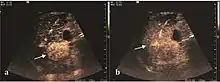

The suggestive appearance of early HCC on 2D ultrasound examination is that of hypoechoic nodule, with distinct pattern, developed on cirrhotic liver. Hypoechoic appearance is characteristic of moderate/poorly differentiated HCC, with low or absent fatty changes. Rarely, HCC may appear isoechoic, consist of a tumor type with a higher degree of differentiation and therefore with slower development. Another common aspect is "bright loop" or "nodule-in-nodule" appearance, hypoechoic nodules in a hyperechoic tumor.

On CEUS examination, early HCC has an iso- or hypervascular appearance during the arterial phase followed by wash out during portal venous and late phase. There are studies showing that the wash out process is directly correlated with the size and features of neoplastic circulatory bed. Thus, highly differentiated HCC illustrates the phenomenon of late or even very late "wash out" while poorly differentiated HCC has an accelerated wash out at the end of arterial phase. It is therefore mandatory to analyze all these three phases of CEUS examination for a proper characterization of liver nodules. Tumor wash out at the end of the arterial phase allows the HCC diagnosis with a predictability of 89.5%. Some authors consider that early pronounced contrast enhancement of a nodule within 1–2 cm developed on a cirrhotic liver is sufficient for HCC diagnosis. These results prove that for a correct characterization of the lesions it is necessary to extend the examination time to 5 minutes or even longer.